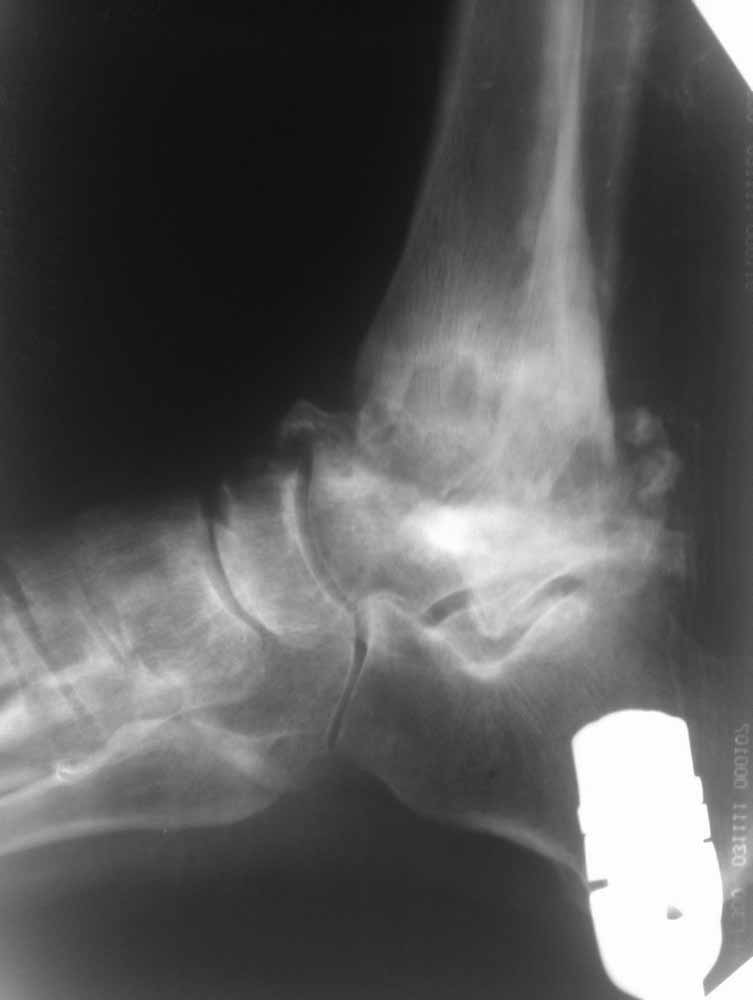

Re: Дефартроз голеностопа+перелом пилона+перелом тарана?

Жалобы со стороны второго сустава есть - прыгать на костылях до томографа без опоры на левую стопу пациенту было больно.

Зачем вытяжение - эффект на рентгенограммах виден.

Склоняемся к мысли, что все таки Charcot's Joint.

Планируем артродез стержнем правого голеностопа + аппарат на левый голеностоп.

Остается вопрос - как монтировать ? одномоментно корректировать или все таки постепенно аппаратом?